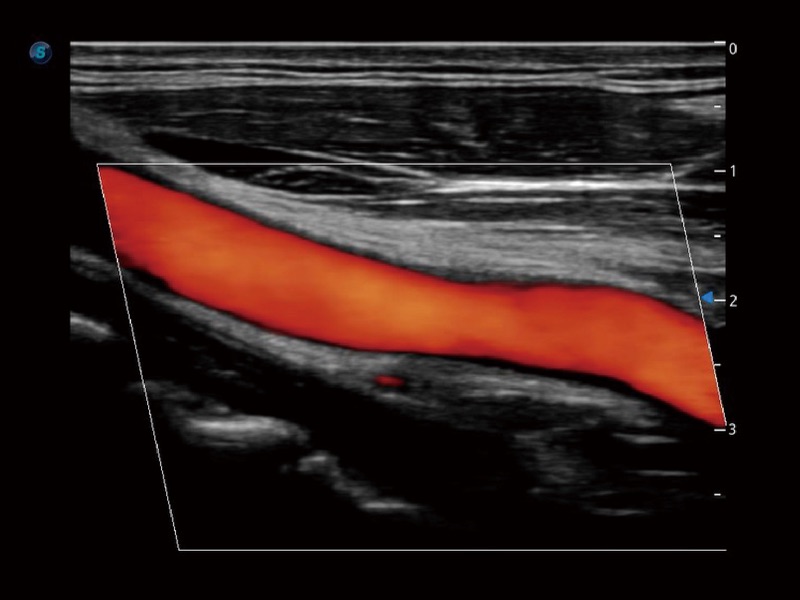

• SR Flow 高分辨率血流成像技术

高分辨率血流成像技术提高了对低速血流信号的检测能力。在提高空间分辨率的同时,也克服了血流外溢现象,为用户提供更加真实的血流动力学信息。

• 心血管应用

• 血管内中膜自动测量 Auto IMT

血管内中膜的厚度值是预测心血管疾病风险的重要指标,Auto IMT可以实现血管近场和远场内中膜厚度的自动测量,为临床提供快捷有效的诊断工具。

临床图